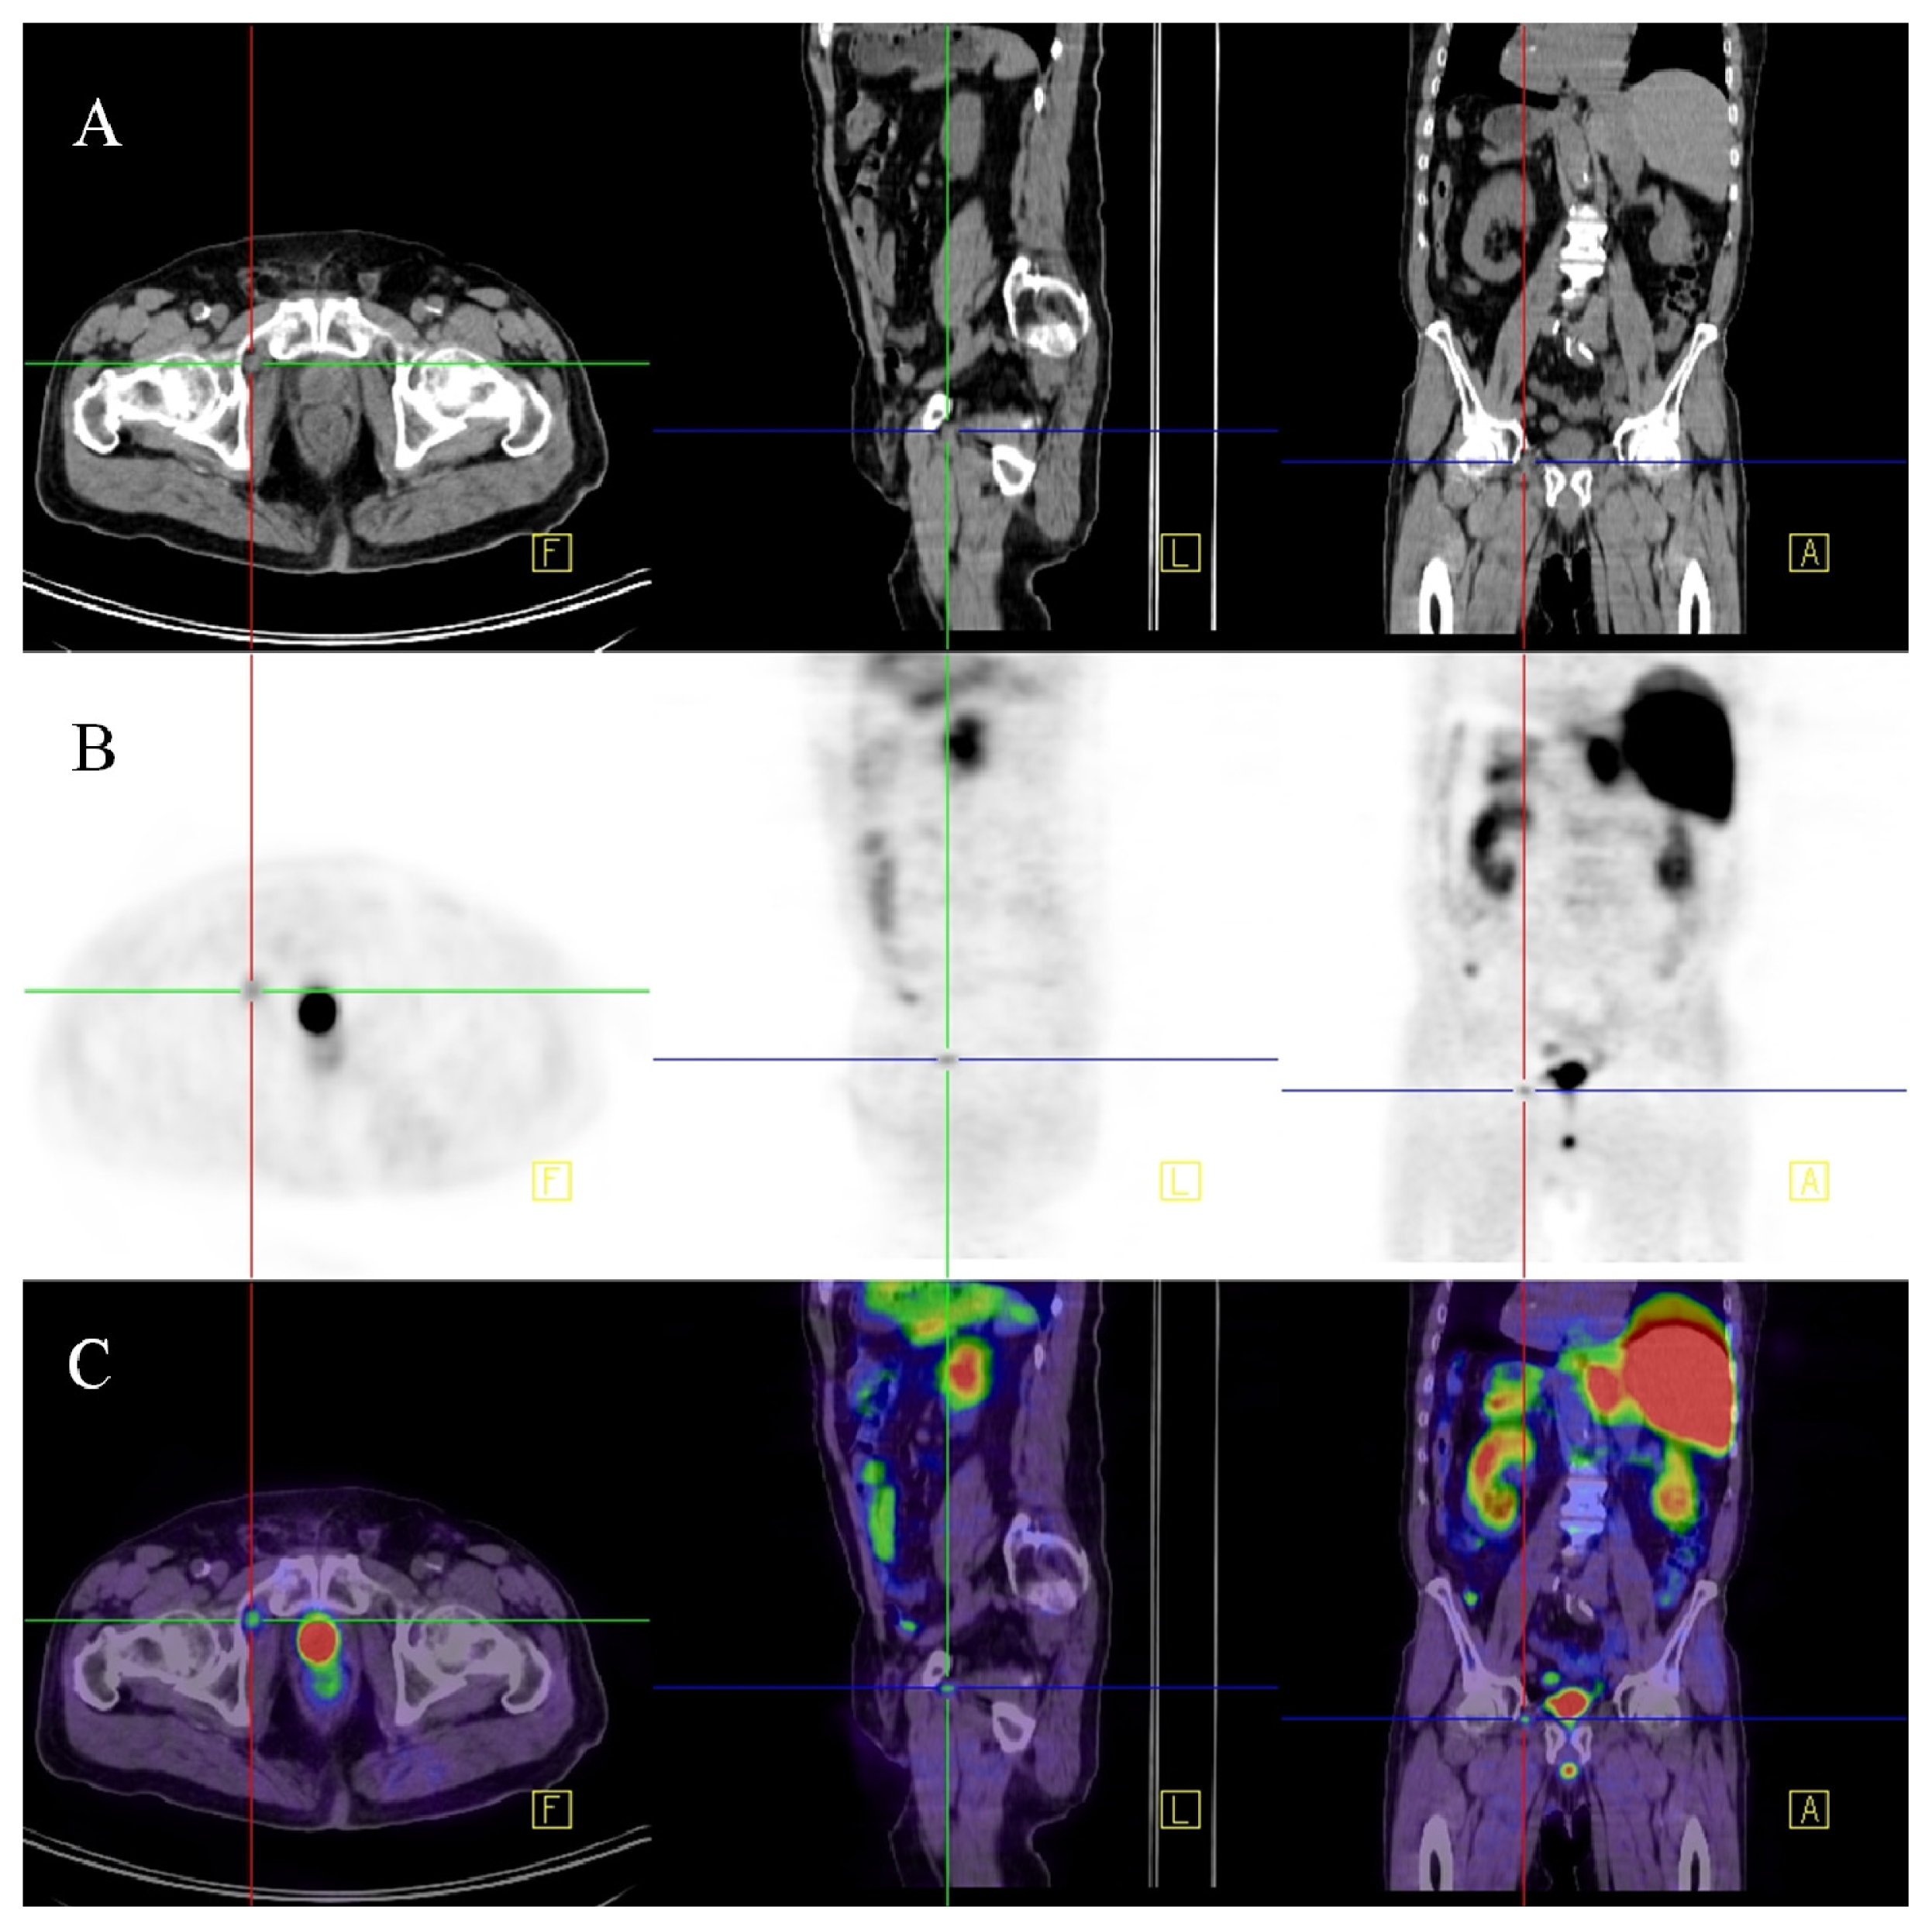

- Afshar-Oromich, A.; Malcher, A.; Eder, M.; Eisenhut, M.; Linhart, H.G.; Hadaschikc, B.A.; Holland-Letz, T.; Giesel, F.L.; Kratochwil, C.; Haufe, S.; et al. Pet imaging with a [68GA] gallium-labelled PSMA ligand for the diagnosis of prostate cancer: biodistribution in humans and first evaluation of tumour lesions. Eur. J. Nucl. Med. Mol. Imaging 2013, 40, 486–495. [Google Scholar]